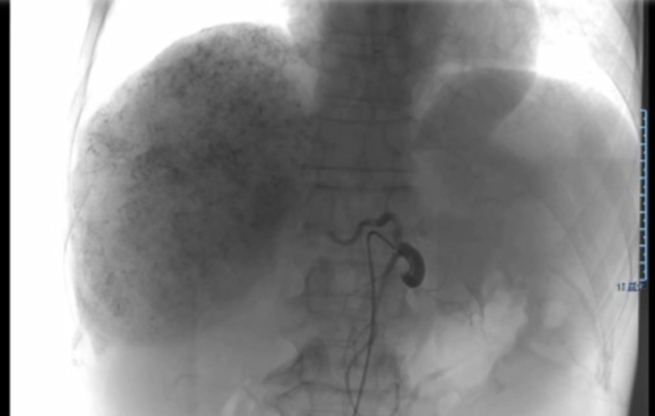

2019-4-26,TACE(雷替曲塞、多柔比星脂质体化疗+碘油、PVA/微球超选栓塞),每月1次,2019-6-14进行第二次介入,2019-7-26进行第三次介入,2019-10-14进行术后第一次介入,2020-4-15术后第二次介入。

治疗方案:TACE+靶向+免疫

➣ 病灶及受累血管局限在右半肝;Child-Pugh A级;剩余肝体积 / 标准肝体积 > 40%;ICG 15分钟滞留率=25%。因此,不可手术切除。